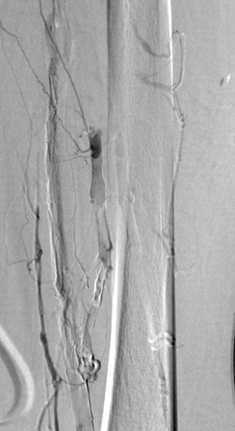

Venografía de la vena femoral tras trombectomía fármaco-mecánica (PMT) mediante la técnica Power Pulse Delivery (se usaron 15 ml de una solución de 50 mg de tPA  en 500 ml de solución salina natural) seguida por 2 pasadas con el catéter DVX de AngioJet.

Venografía en posición decúbito supino tras introducir 2 veces el catéter DVX de AngioJet. Vena ilíaca externa y vena femoral común del paciente. Estenosis severa de la vena ilíaca común.